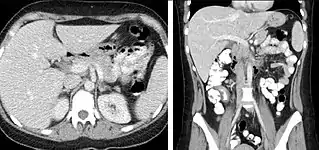

Pancreatic masses

Pancreatic masses are often evaluated using both an early arterial (to evaluate for vascular involvement and thus resectability, figure 9a) and a later “pancreatic” phase (which optimizes pancreatic parenchymal enhancement and thus is best at differentiating pancreatic tumors from pancreatic parenchyma, figure 9b). Pancreatic adenocarcinoma typically is hypoenhancing when compared to the surrounding parenchyma. Most other common pancreatic tumors are hypervascular with avid enhancement (such as pancreatic neuroendocrine tumors) and appear brighter than the surrounding pancreatic parenchyma after the injection of intravenous contrast material.